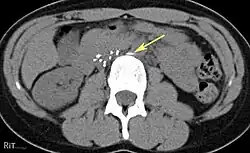

An inferior vena cava filter is a medical device made of metal that is implanted by vascular surgeons or interventional radiologists into the inferior vena cava to prevent a life-threatening pulmonary embolism (PE) or venous thromboembolism (VTE).[2][3]

The filter is designed to trap a blood clot and prevent its travel to the lung where it would form a pulmonary embolism.[4][3] Their effectiveness and safety profile is well established, and they may be used when anticoagulant treatment is not sufficient.[5]

IVC filters are placed endovascularly, meaning that they are inserted via the blood vessels. Historically, IVC filters were placed surgically, but with modern filters that can be compressed into much thinner catheters, access to the venous system can be obtained via the femoral vein (the large vein in the groin), the internal jugular vein (the large vein in the neck) or the arm veins with one design. Choice of route depends mainly on the number and location of any blood clot within the venous system. To place the filter, a catheter is guided into the IVC using fluoroscopic guidance, then the filter is pushed through the catheter and deployed into the desired location, usually just below the junction of the IVC and the lowest renal vein.[44]

Review of prior cross-sectional imaging or a venogram of the IVC is performed before deploying the filter to assess for potential anatomic variations, thrombi within the IVC, or areas of stenoses, as well as to estimate the diameter of the IVC. Rarely, ultrasound-guided placement is preferred in the setting of contrast allergy, chronic kidney disease, and when patient immobility is desired. The size of the IVC may affect which filter is deployed, as some (such as the Birds Nest) are approved to accommodate larger cavae. There are situations where the filter is placed above the renal veins (e.g. pregnant patients or women of childbearing age, renal or gonadal vein thromboses, etc.). Also, if there is duplication of the IVC, the filter is placed above the confluence of the two IVCs [45] or a filter can be placed within each IVC.[46]